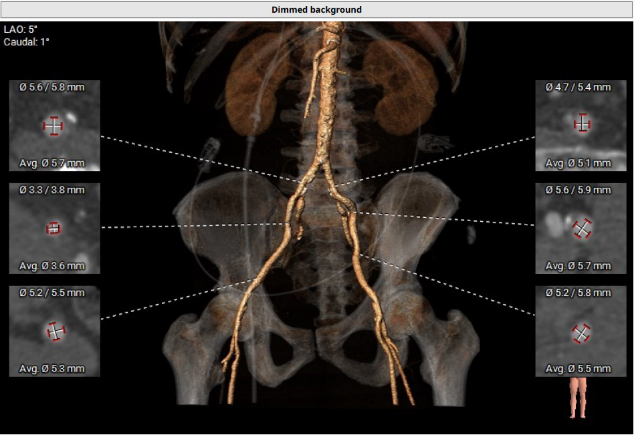

外周血管评估

• 外周血管入路最狭窄处直径无法满足经动脉TAVR手术器械的输送要求。

• 全麻下经心尖入路,植入Xcor™-23经导管主动脉瓣膜。使用较小球囊(18mm)预扩病变,同时再次评估/确认钙化情况及人工瓣膜尺寸选择合理性。